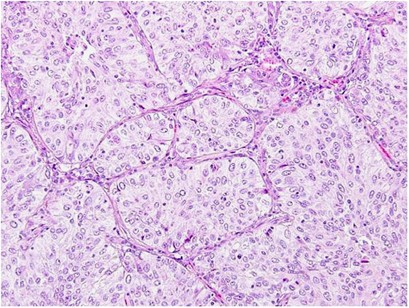

Cribriform pattern tumors had invasive fused tumor glands with back-to-back, poorly formed glandular spaces lacking intervening stroma or invasive tumor nests that produce small glandular lumina without solid components (Figure 1a–c). These tumors sometimes have a ‘cookie-cutter’ pattern of gland-like spaces (Figure 1d). In contrast, the usual acinar pattern had well-defined individual tumor glands with well-formed glandular lumina (Figure 2a–d). Solid pattern tumors had invasive solid tumor nests without glandular space (Figure 3). The cribriform pattern was present in 25% of all tumors (n=262); among tumors with cribriform pattern, the average percentage of cribriform component was 21% (median, 18%; range, 5–80%). Table 2 presents the numbers of cases of each predominant histologic subtype classified according to the IASLC/ATS/ERS classification, as well as with the cribriform pattern as an additional subtype. With the cribriform pattern added as a subtype, tumors were identified in the following numbers: 46 (4%) cribriform predominant, 2 (0.2%) adenocarcinoma in situ, 34 (3%) minimally invasive adenocarcinoma, 106 (10%) lepidic predominant, 356 (34%) acinar predominant, 242 (23%) papillary predominant, 60 (6%) micropapillary predominant, 139 (13%) solid predominant, 44 (4%) invasive mucinous, and 9 (1%) colloid predominant. After the addition of the cribriform subtype, 46 (11%) of the acinar predominant tumors (according to the original IASLC/ATS/ERS classification; n=411) were reclassified as cribriform predominant, 3 (0.7%) were reclassified as lepidic predominant, 3 (0.7%) were reclassified as papillary predominant, and 3 (0.7%) were reclassified as solid predominant.

Cribriform pattern in lung adenocarcinoma. (a) Invasive tumor nests with poorly formed, small-to-intermediate-sized glandular spaces lacking intervening stroma. (b) Invasive fused tumor glands of intermediate-sized glandular spaces with extracellular mucin, lacking intervening stroma or having very thin stroma in limited areas between glandular spaces. (c) Invasive tumor nests with poorly formed, intermediate-sized glandular spaces with back-to-back formations. (d) Invasive tumor nests with a few poorly formed, small-sized glandular spaces with ‘cookie-cutter’ patterns.

Acinar pattern in lung adenocarcinoma. (a) Simple tumor glands of tumor cells with mild nuclear atypia and desmoplastic stroma. (b) Simple tumor glands of tumor cells with moderate nuclear atypia. (c) Large, simple tumor glands with clear cytoplasm and intraglandular mucin. (d) Crowded glands mixed with simple and some complex glandular spaces but having intervening stroma in most areas between glandular spaces.